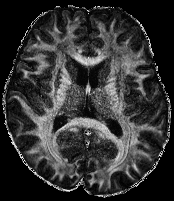

In Figure 1 we show a toy example of misjudgments that occur when evaluating the quality of a 2D MRI scan compared to degraded versions of the same image with standard measures. PSNR even yields the same value for all the very different degradations, and all of the standard measures fail in the judgement of massive local information loss (d), as well as in the judgment of stochastic noise (e) versus block artefacts (f). This toy example served as an inspiration to study the behavior of the standard measures in real life medical imaging tasks.

Figure 1: Illustrative toy example of problems occuring when using PSNR/SSIM/LPIPS for the evaluation of medical images in FR setting. Degradations have been added artificially to the reference (a) MRI scan: contrast enhancement (b), brightness change (c), hole (d), Gaussian White noise (e), jpeg compression (f). PSNR yields the same value for all degradations, SSIM and LPIPS fail to identify the hole (d), and misjudge the quality of (e) and (f).